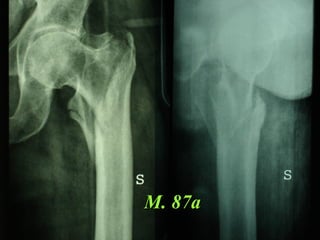

La placca a compressione percutanea (PC.C.P.) di Gotfried è un mezzo di sintesi studiato per assicurare un “impattamento controllato” delle fratture pertrocanteriche grazie alle due viti telescopiche prossimali che garantiscono una ottima stabilità rotazionale

Tradizionalmente si ritiene importante per la stabilità delle fratture pertrocanteriche l’integrità della parte mediale della metafisi prossimale del femore

In realtà la zona più importante per la ricostruzione di questo tipo di fratture è il muro laterale contro il quale si impatta il frammento metaepifisario mediale

Se il muro laterale è rotto o viene lesionato durante la sintesi , come spesso accade in fase di applicazione della vite cefalica dei chiodi endomidollari o della vite-placca, andremo incontro al collasso della frattura e ad un conseguente lungo periodo di impotenza funzionale

Con la placca di Gotfried non si è mai riscontrato un danno iatrogeno del muro laterale e nessun collasso della frattura.Ciò è dovuto al fatto che i fori per l’applicazione delle due viti prossimali sono di piccolo diametro (9 mm) rispetto ai 16-32 mm necessari per introdurre la vite cefalica di un chiodo endomidollare o di una vite-placca a compressione.

La placca PC.C.P. viene inoltre applicata per via percutanea attraverso due piccole incisioni ottenendo in tal modo un minimo trauma chirurgico ed una  perdita di sangue estremamente ridotta in pazienti che per l’età  sono già in condizioni  critiche

Dal Gennaio 2005 ad Agosto 2006 110  placche di Gotfried Età media  : 78 anni (range 29-94) Tempo chirurgico: 30 minuti (range 12-45) IMMEDIATA CONCESSIONE DEL CARICO

M. 87a